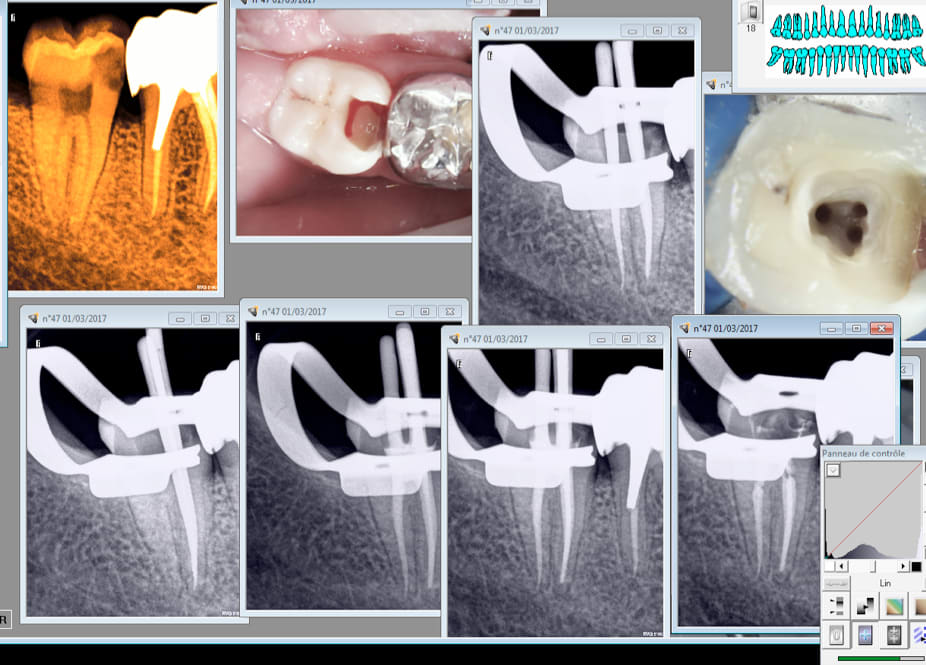

Bon alors au vu des radios d'il y a 10 mois et de la radio initiale c'est moi qui a merdé en faisant une perfo en mésio lingual ou il y avait une putain de résorbtion interne à cet endroit ?

Dent très douloureuse sans raison apparente. On a l'impression qu'il y a une zone radio claire en mésial. A l'ouverture de la chambre ca saignait à bloc !

Résorption visible sur ta cavité d'accès et à la radio , la dent est asymptomatique maintenant non ?

Je dirais plutôt résorbtion externe, mais le résultat est le même. Ce qui est con c'est qu'on le voit généralement après.....dans un premier temps on pense toujours à une superposition de la trame osseuse sur la projection radio. dejà eu quelques cas...

Celle là ca va mieux. -) Pas réussi à avoir la meme image en cone scellé et condensé en mésial que la radio cone en place.